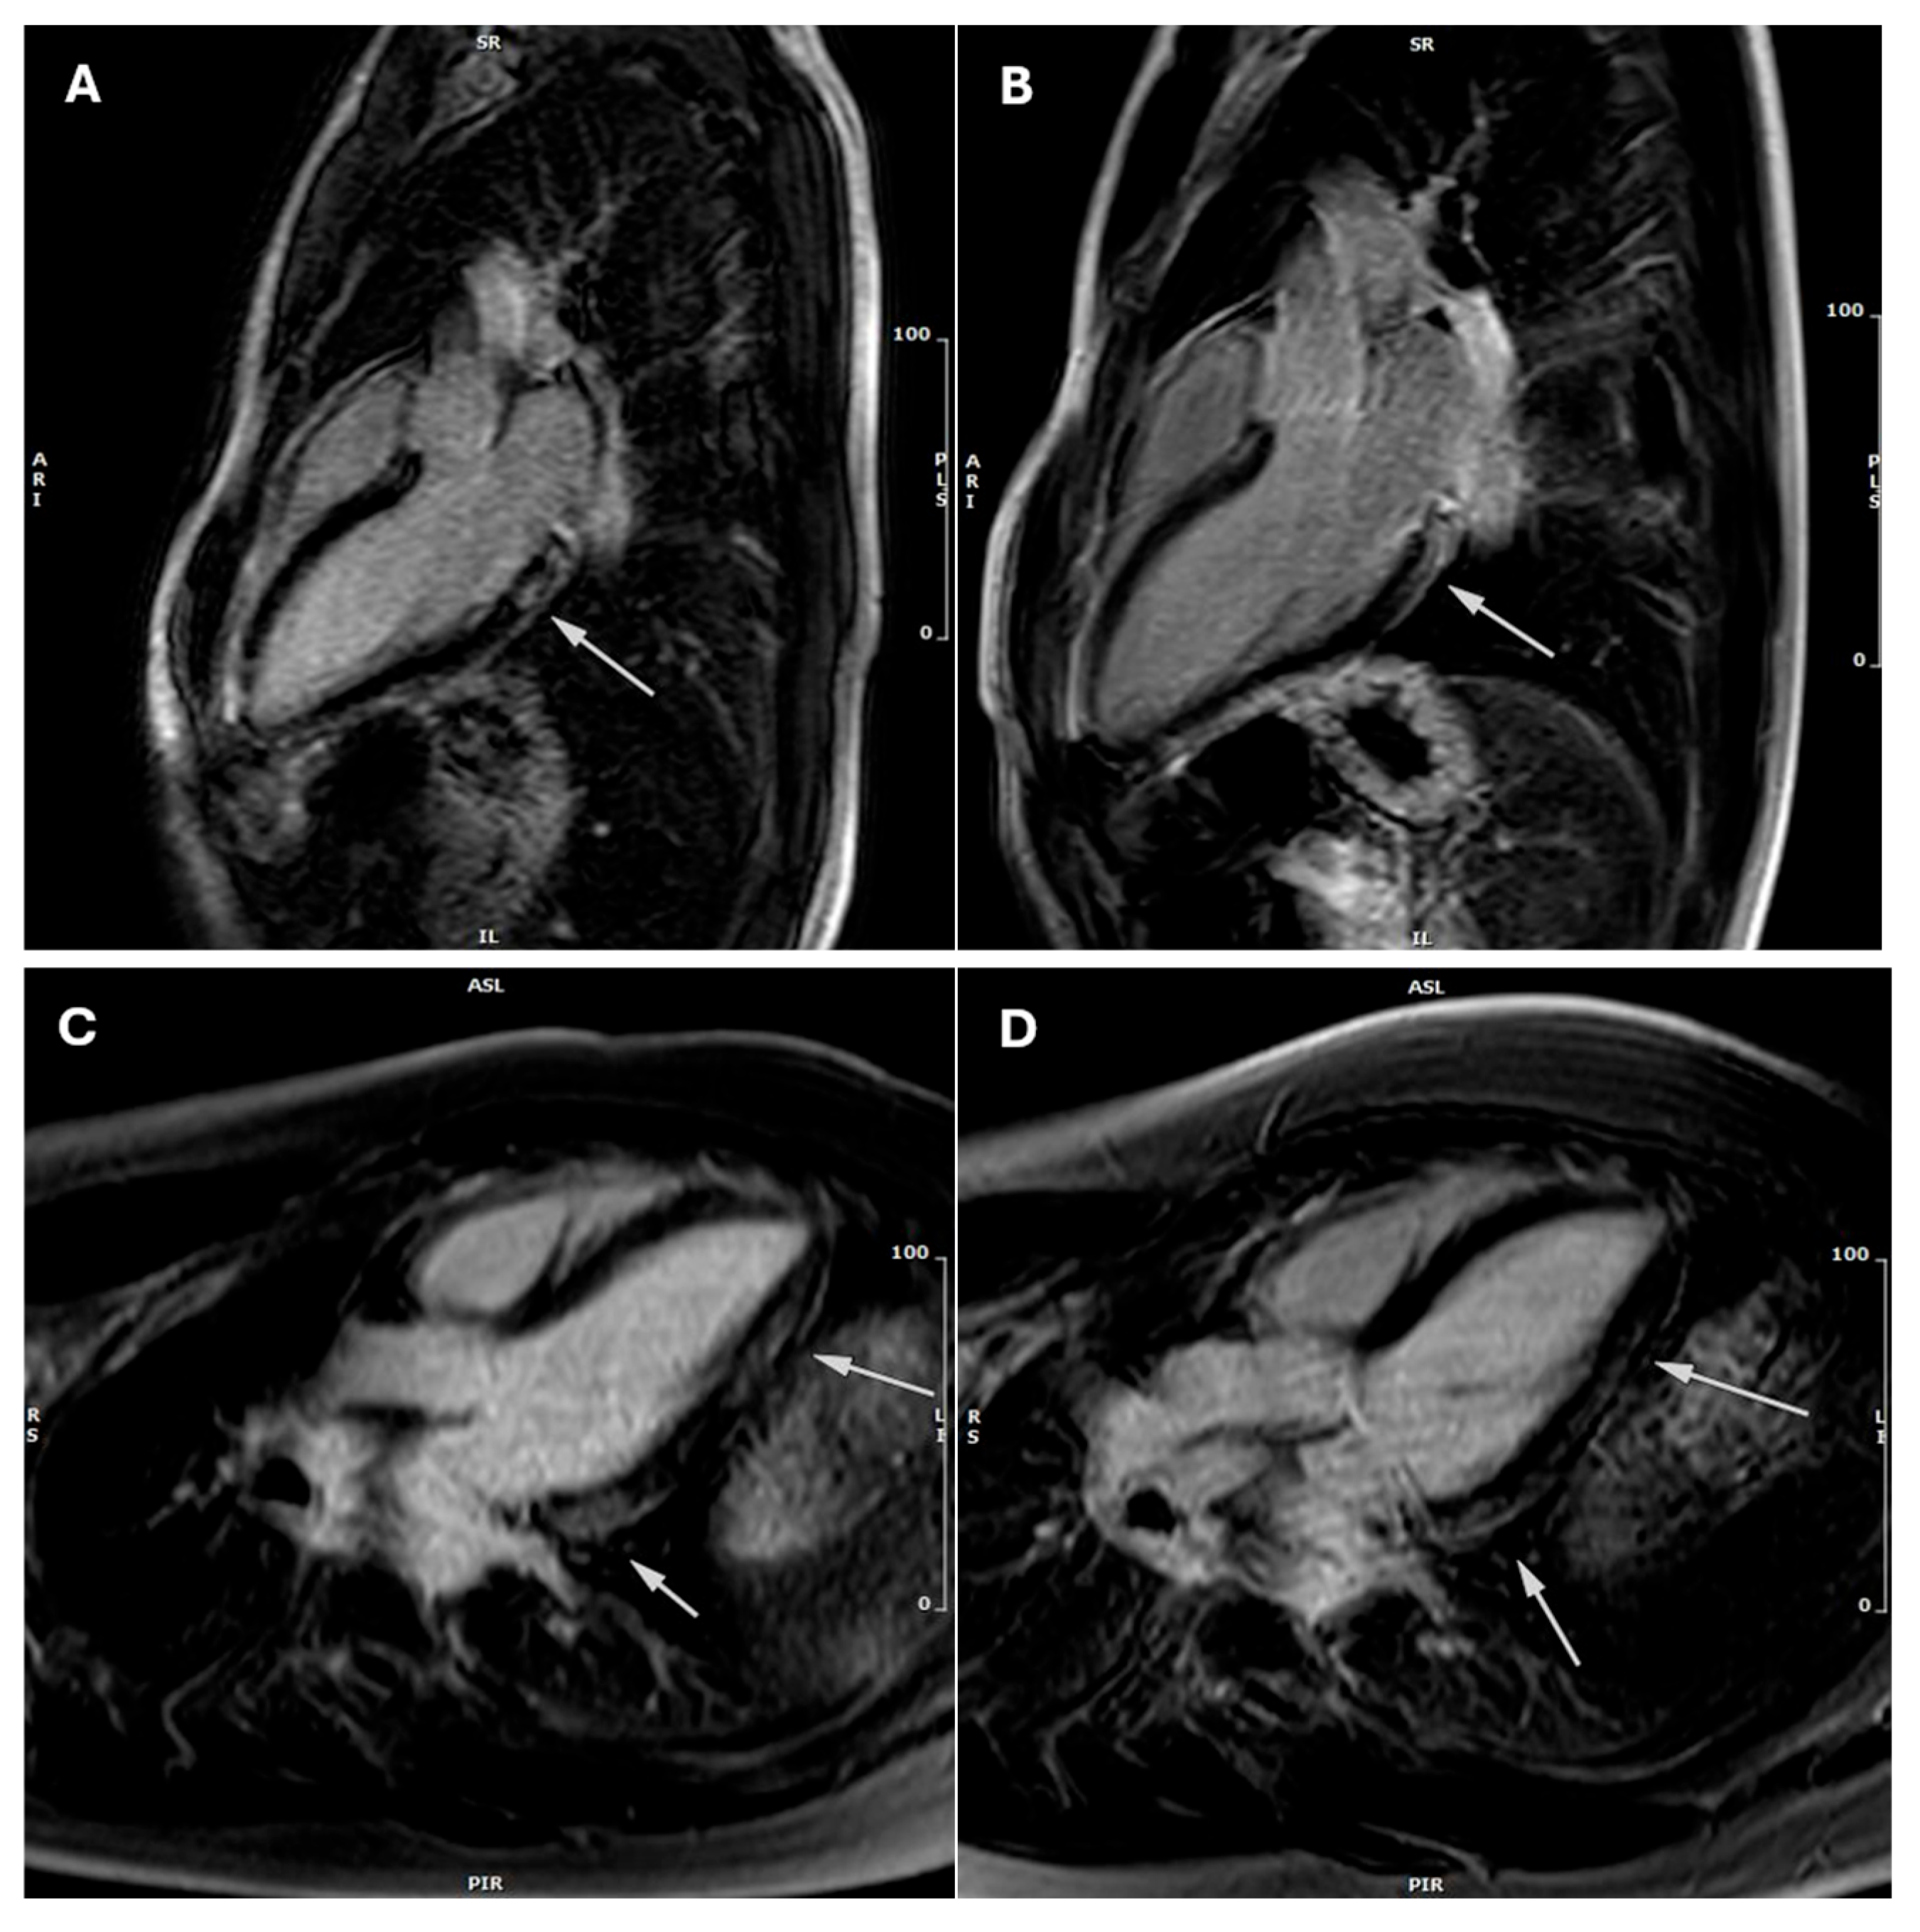

Figure 2. Three-chamber late gadolinium enhancement (LGE) cardiac magnetic resonance (CMR) images of two athletes at baseline and follow-up. (A) LGE-positive image from the first athlete at baseline CMR-1 showing limited involvement of the basal inferolateral wall of the left ventricle. (B) LGE-negative image from the same athlete at follow-up CMR-2 demonstrating resolution of LGE. (C) LGE-positive image from a second athlete at baseline CMR-1 displaying extensive involvement of the inferolateral wall of the left ventricle. (D) LGE-positive follow-up image of the second athlete at CMR-2 showing unchanged extent of LGE. The arrows delineate the regions exhibiting LGE.